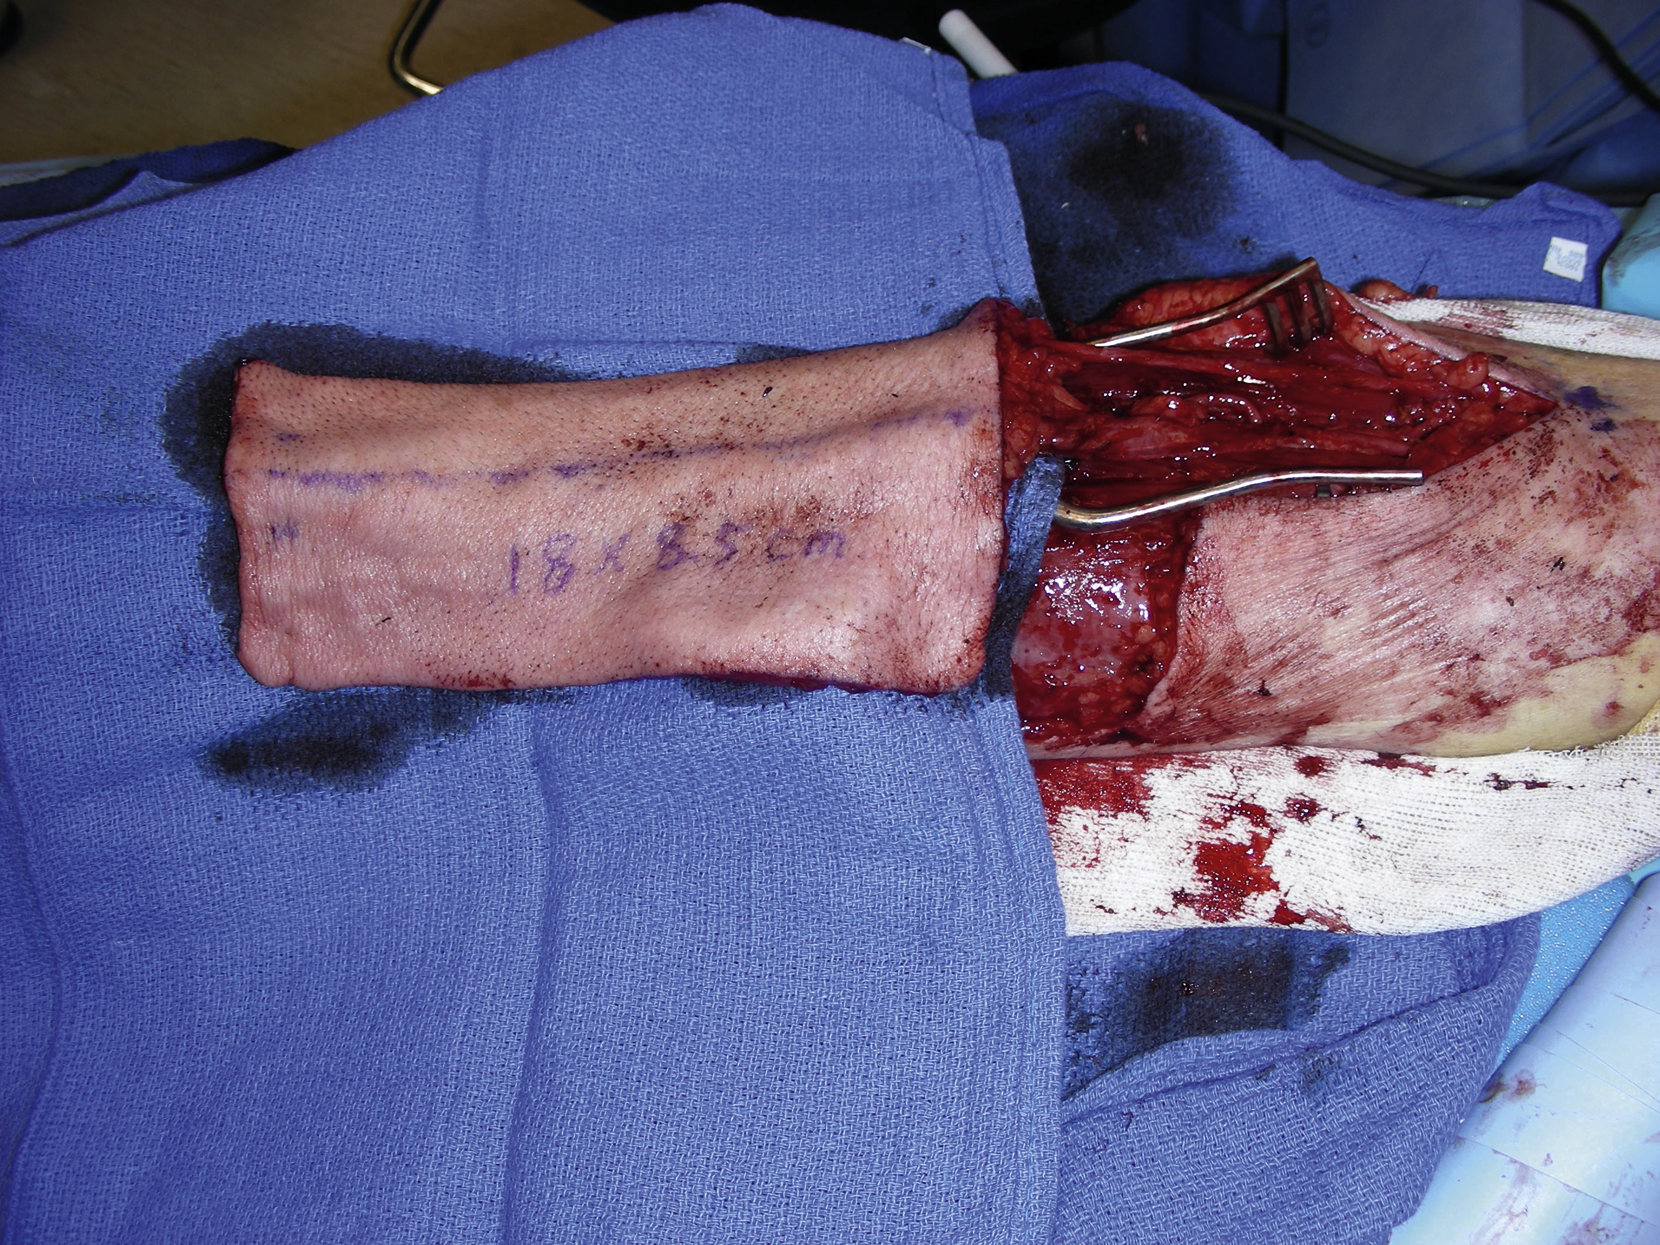

The right radial forearm flap was harvested by the plastic surgery service. The flap was marked out on the volar surface of the forearm and measured 18 × 8.5 cm ( Fig. 25.2 ). An intraoperative handheld Doppler was done to confirm pulses in the arch and the thumb with occlusion of the radial artery. The flap dissection was initially performed to the subcutaneous tissue. The suprafascial dissection was then performed and the cephalic vein, the radial artery, and its venae comitantes were identified and divided at the level of the wrist crease. The flap was raised from the ulnar to radial forearm and the septocutaneous perforators from the radial artery were preserved. This part of the flap dissection was performed under tourniquet control. The flap was raised from distal to proximal and the radial artery was dissected free to the level of the bifurcation of the brachial artery ( Fig. 25.3 ). The flap was then tubularized over a Hegar dilator, putting the skin at the internal lining of the flap and constructing this with a running dermal 3-0 Vicryl suture for a watertight seal. The tube was approximately 3 cm in diameter and 18 cm long ( Fig. 25.4 ).